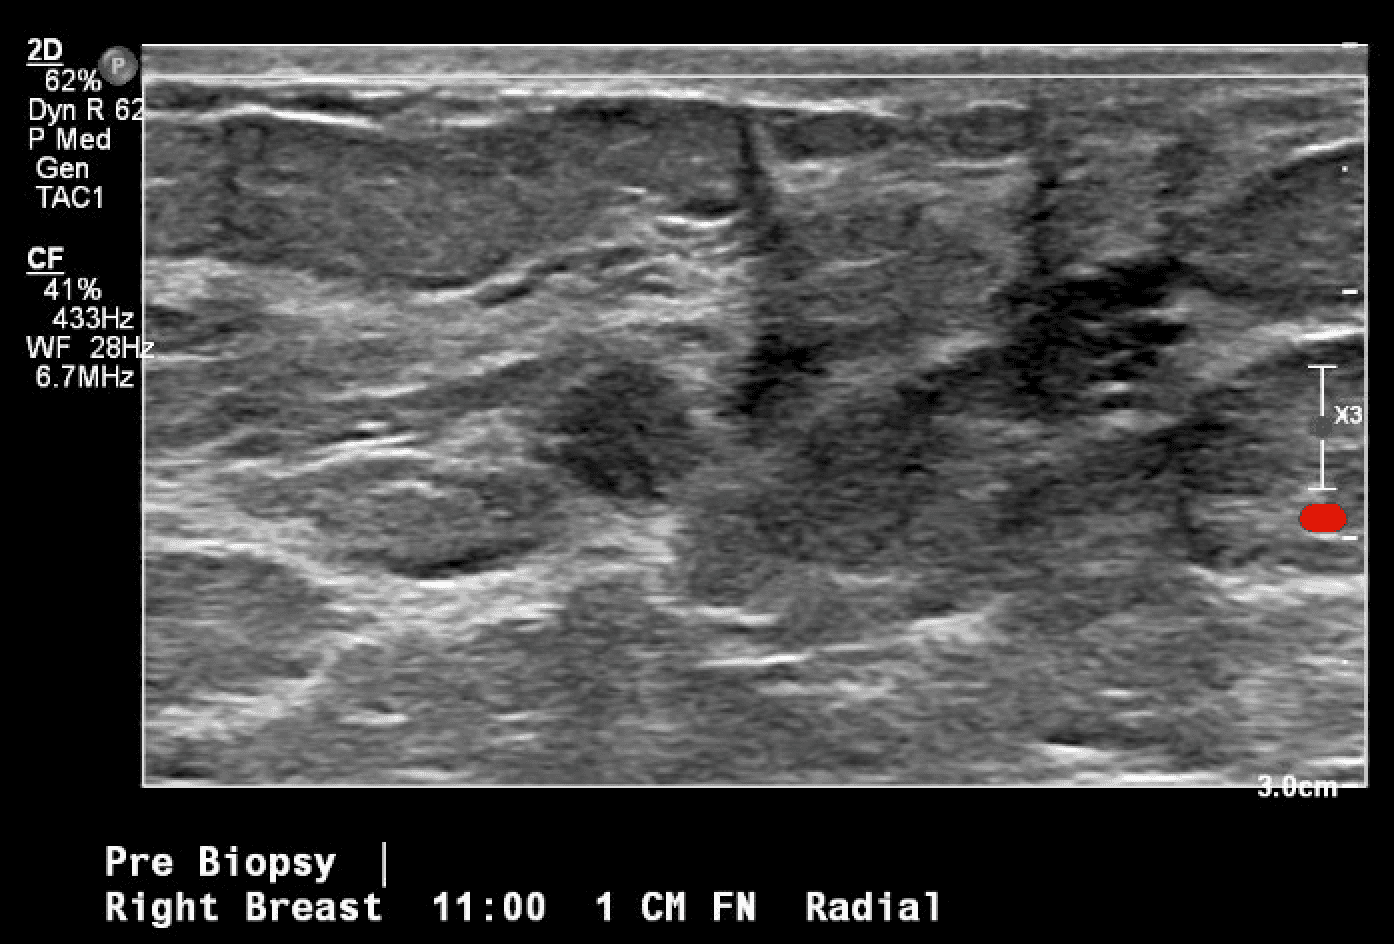

Patient is a 46-year-old premenopausal female with no other contributing past medical or surgical history who presented initially to the breast surgery clinic after her annual screening mammogram discovered a nonpalpable right breast mass measuring 0.6 x 0.8 x 0.7 cm at 11 o’clock (oc), 1 cm from the nipple (FTN) (Figure 1). She had three previous screening mammograms without any notable findings. The screening mammogram was declared inconclusive (BI-RADS 0), and a breast ultrasound was completed with similar findings. Further discussion with the patient revealed that there had been some bloody discharge seen in the right side of her bra over the last few months, but no other concerns or symptoms. Given the inconclusive imaging findings, it was decided to perform a diagnostic mammogram for a more specific assessment (Figures 2a and 2b) following an ultrasound-guided core-needle biopsy and localizing clip placement for a tissue diagnosis (Figure 3). Pathology revealed an intraductal papilloma with ductal hyperplasia and apocrine metaplasia without atypia. Given her continued bloody nipple discharge, there was concern for possible underlying premalignant cells (discussed more later); thus, it was recommended that the patient undergo partial mastectomy. The mass remained nonpalpable; therefore, a Savi Scout would be placed just before operative intervention to help localize the area of concern.

Figure 3. Ultrasound-guided localization and biopsy of the breast mass in question, first seen on screening mammogram. Post-biopsy image includes typical tissue changes seen once a core-needle biopsy is performed (hash mark).